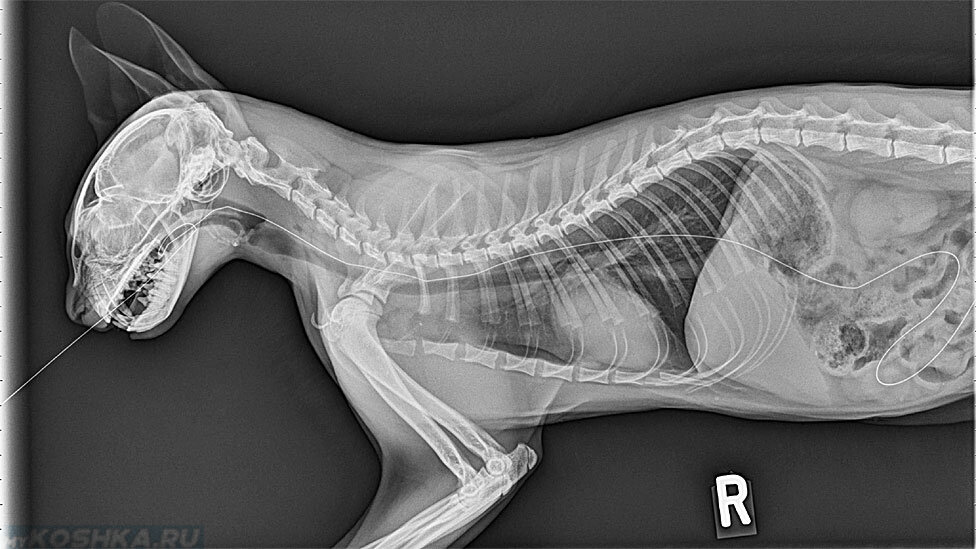

Рентгеновские снимки анатомии собак: строение и здоровье